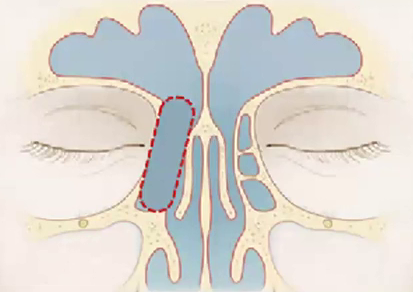

Cite os limites do recesso do seio frontal:

• Anterior = Frontal beak (e Agger Nasi).

• Posterior = Bula etmoidal

• Medial = Porção vertical da concha média

• Lateral = Lâmina Papirácea